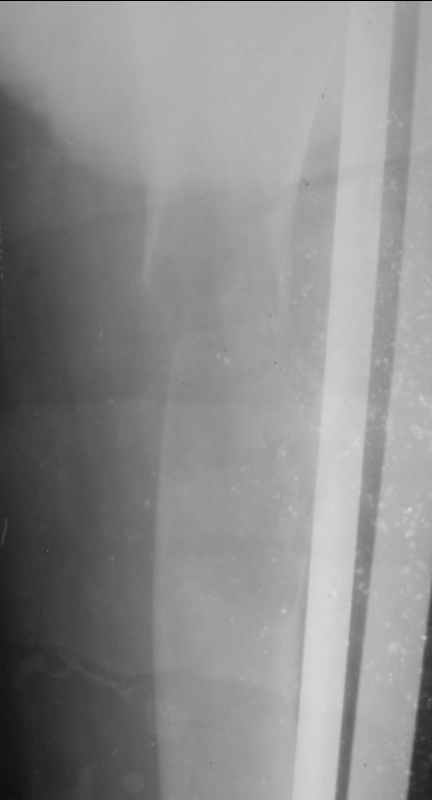

Добрый день, уважаемые коллеги!Мои коллеги из Грозного просили проконсультировать случай больного М. 26 лет. Боли беспокоили около 1 года в области подвздошной ости слева, по поводу чего неоднократно обледовался - неоднократно выполнены снимки тазобедренного сустава. Снимки бедра не выполнялись. 1,5 месяца назад, находясь на работе, поднимаясь по лестнице в больнице почувствовал сильную боль, упал. При этом произошел перелом верхней трети бедра. На рентенограммах, представленных во вложении обнаружен патологический перелом. Траматологи расценивают это как кистозную дисплазию, хотя уверенности нет. Сейчас находится на склетном вытяжении. Каков прогноз заболевания? Верна ли тактика, показаны ли в будущем какие-то вмешательства?Заранее спасибо.С наилучшими пожеланиями, Бекхан.

Уважаемый Бекхан! По клинике и рентгенограммам (на снимках 1010139 и 1010140 прослеживается козырек) у пациента более всего вероятна опухоль Кодмана (морфологический характер можно уточнить по биопсии).

Для хондробластом, насколько мне известно, не характерна ни диафизарная локализация, ни рентгнологическая картина, демонстирирующая инвазивный рост.

По представленным рентгенограммам процесс очень смахивает на юношескую дистрофическую костную кисту. Попробуйте дождаться частичной консолидации патологического перелома и сделайте пункцию очага - Вы ничем не рискуете. В полости скорее всего окажется кровь без давления. Одномоментно производится биопсия стенки очага режущим шлямбуром. Гистологическое подтвеждение наличия дистрофического процесса позволит Вам в дальнейшем выполнить аллопластику полости кисты с предварительной корытообразной резекцией (см. Волков М.В). Местоположение очага очень характерно для ЮДКК.

Да, костные кисты там бывают, но представленное их не сильно напоминает.

На мой взгляд, рентгенологическая картина все же напоминает солитарную кисту. В похожей ситуации мы выполнили (на фоне патологического перелома) васкуляризованную аутопластику малоберцовой костью на сосудистых анастомозах. Наблюдаем уже более 2 лет. Нагрузка на конечность в полном объеме, боли отсутствуют (рентгенограмма в аттачменте).